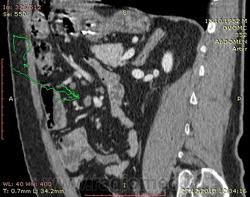

Похоже еще и люмбализация S1 со спондилелизом и антелистезом?

+ истинный антелистез L5 I ст (вместо того, чтоб писать: двустороннее незаращение межсуставной части дуги L5 со смещением тела L5 кпереди до 1/3 ширины тела).

Дегенеративный ретролистез L4 1-й ст. Нисходящая правосторонняя парамедианная грыжа L4-5 диска. И похоже на восходящую в L5-S1, но не достоверно. Фораминальный стеноз L4-5-S1 с очень вероятной компрессией дуральных воронок корешков, особенно слева.

Вообще интраспинально на уровне L4-5-S1 некая каша, не всё могу объяснить листезом. Часть каши может быть за счет мягкотканного компонента вокруг суставных фасеток (наподобие периартроза, гипертрофии связок). Не могу разобраться, рекомендовала бы МРТ.